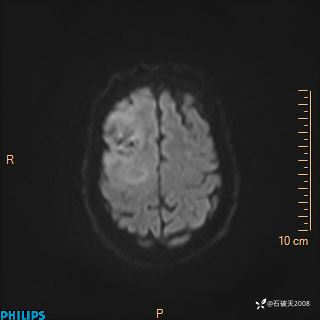

2024.2.21MR

DWI